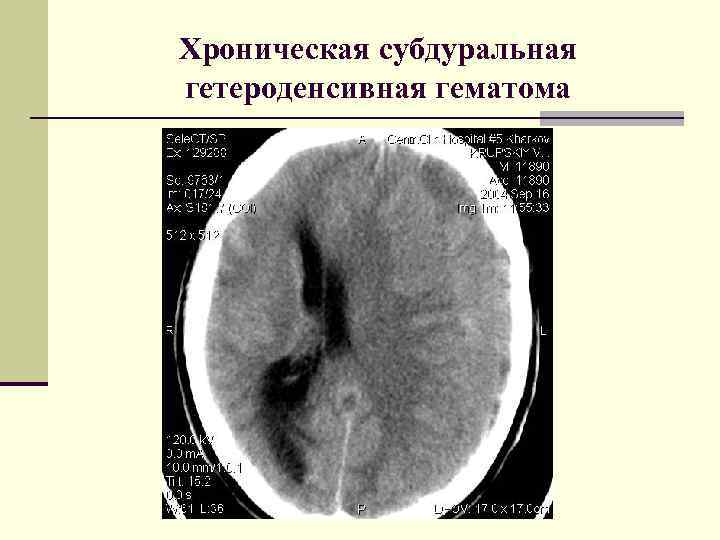

Хронические субдуральные гематомы. Классификация 1. 2. 3. 4. По плотности: Гиподенсивные Гиперденсивные Гетероденсивные Изоденсивные Хронические субдуральные гематомы. Классификация 1. 2. 3. 4. По плотности: Гиподенсивные Гиперденсивные Гетероденсивные Изоденсивные

Хроническая субдуральная гетероденсивная гематома Хроническая субдуральная гетероденсивная гематома